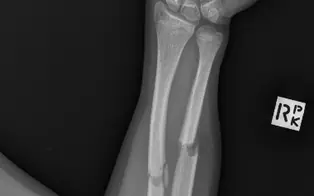

Fracture radius-ulnaire